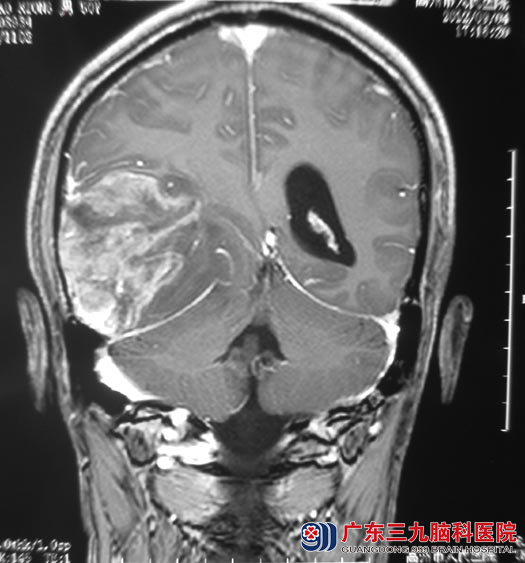

这是肖先生的MR检查,提示:右侧颞枕顶叶占位,大小5.4cm×7.5cm×6.1cm,考虑胶质瘤。是他五天前突然出现双眼视物重影才得以发现。http://www.999brain.com/

家属知情同意后,由鲁明主任主刀在唤醒麻醉下行右侧颞顶枕叶占位切除术,术中导航注册标记肿瘤头皮投影区域,打开硬膜,部分肿瘤组织涌出,显微镜下见肿瘤质软,呈灰红色,血供丰富,超声吸引器吸除肿瘤,脑组织压力下降,见肿瘤边界尚清,前方位于颞叶、后方位于枕叶、上方位于顶叶、下方紧贴小脑幕。手术过程中肖先生的语言、肢体都在活动的状态,切除至见周围正常脑组织。手术后的肖先生经过住院治疗,视物重影症状消失,已康复出院。术后病理结果为:胶质母细胞瘤(WHO IV级)。下一步,他还需要接受进一步的放化疗。